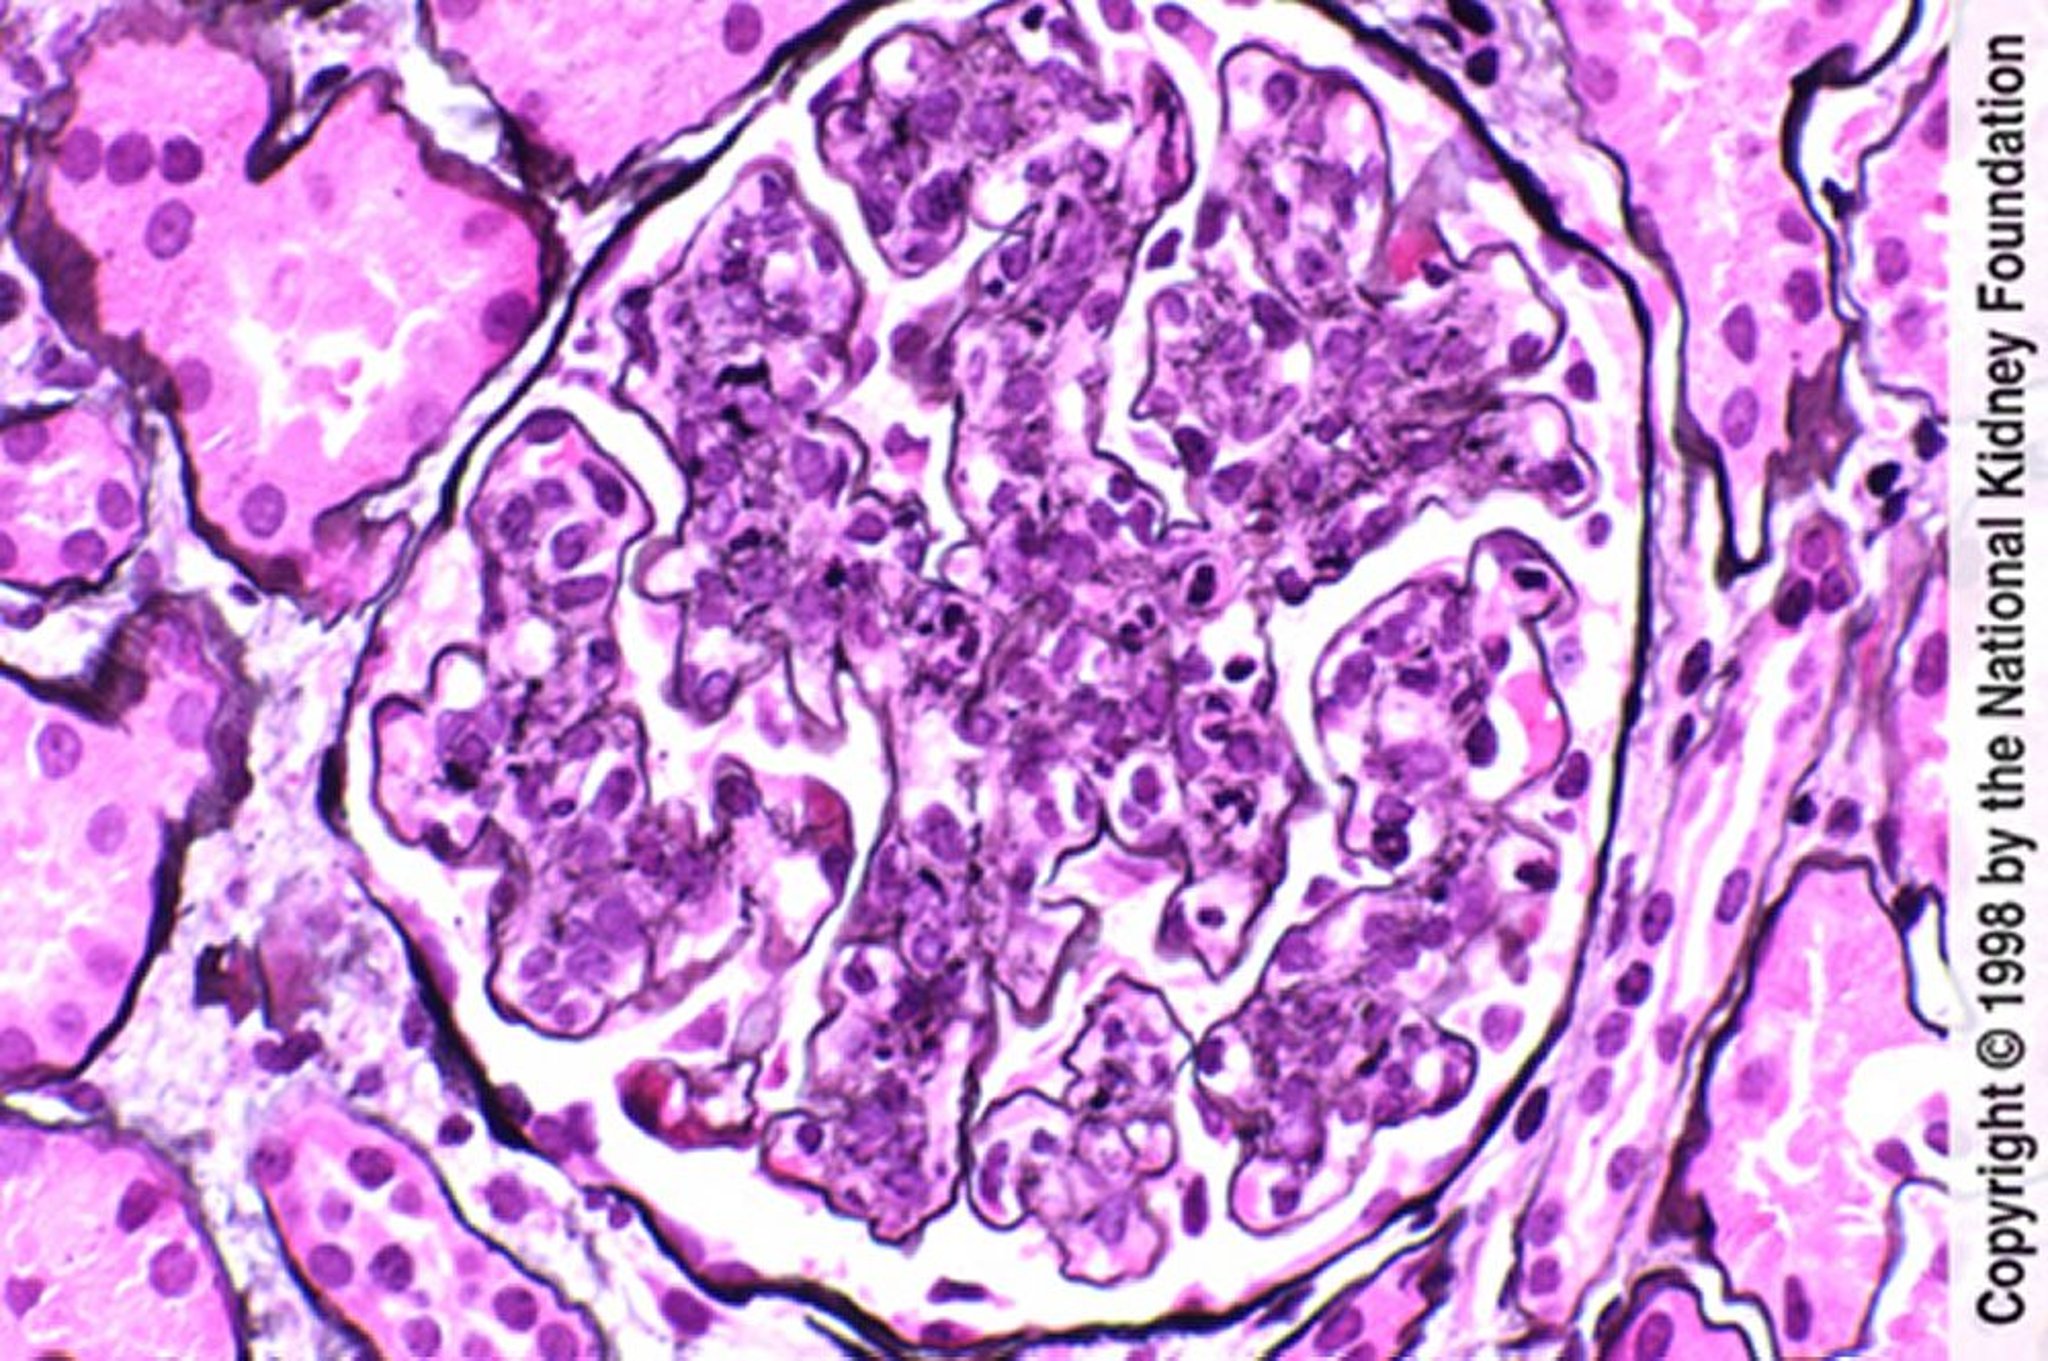

Glomérulonéphrite post-infectieuse (hypercellularité avec infiltration neutrophile)

Hypercellularité endothéliale et mésangiale avec infiltration neutrophile (coloration de Jones à l'argent, ×400).

Image fournie par Agnes Fogo, MD, and the American Journal of Kidney Diseases' Atlas of Renal Pathology (voir www.ajkd.org).